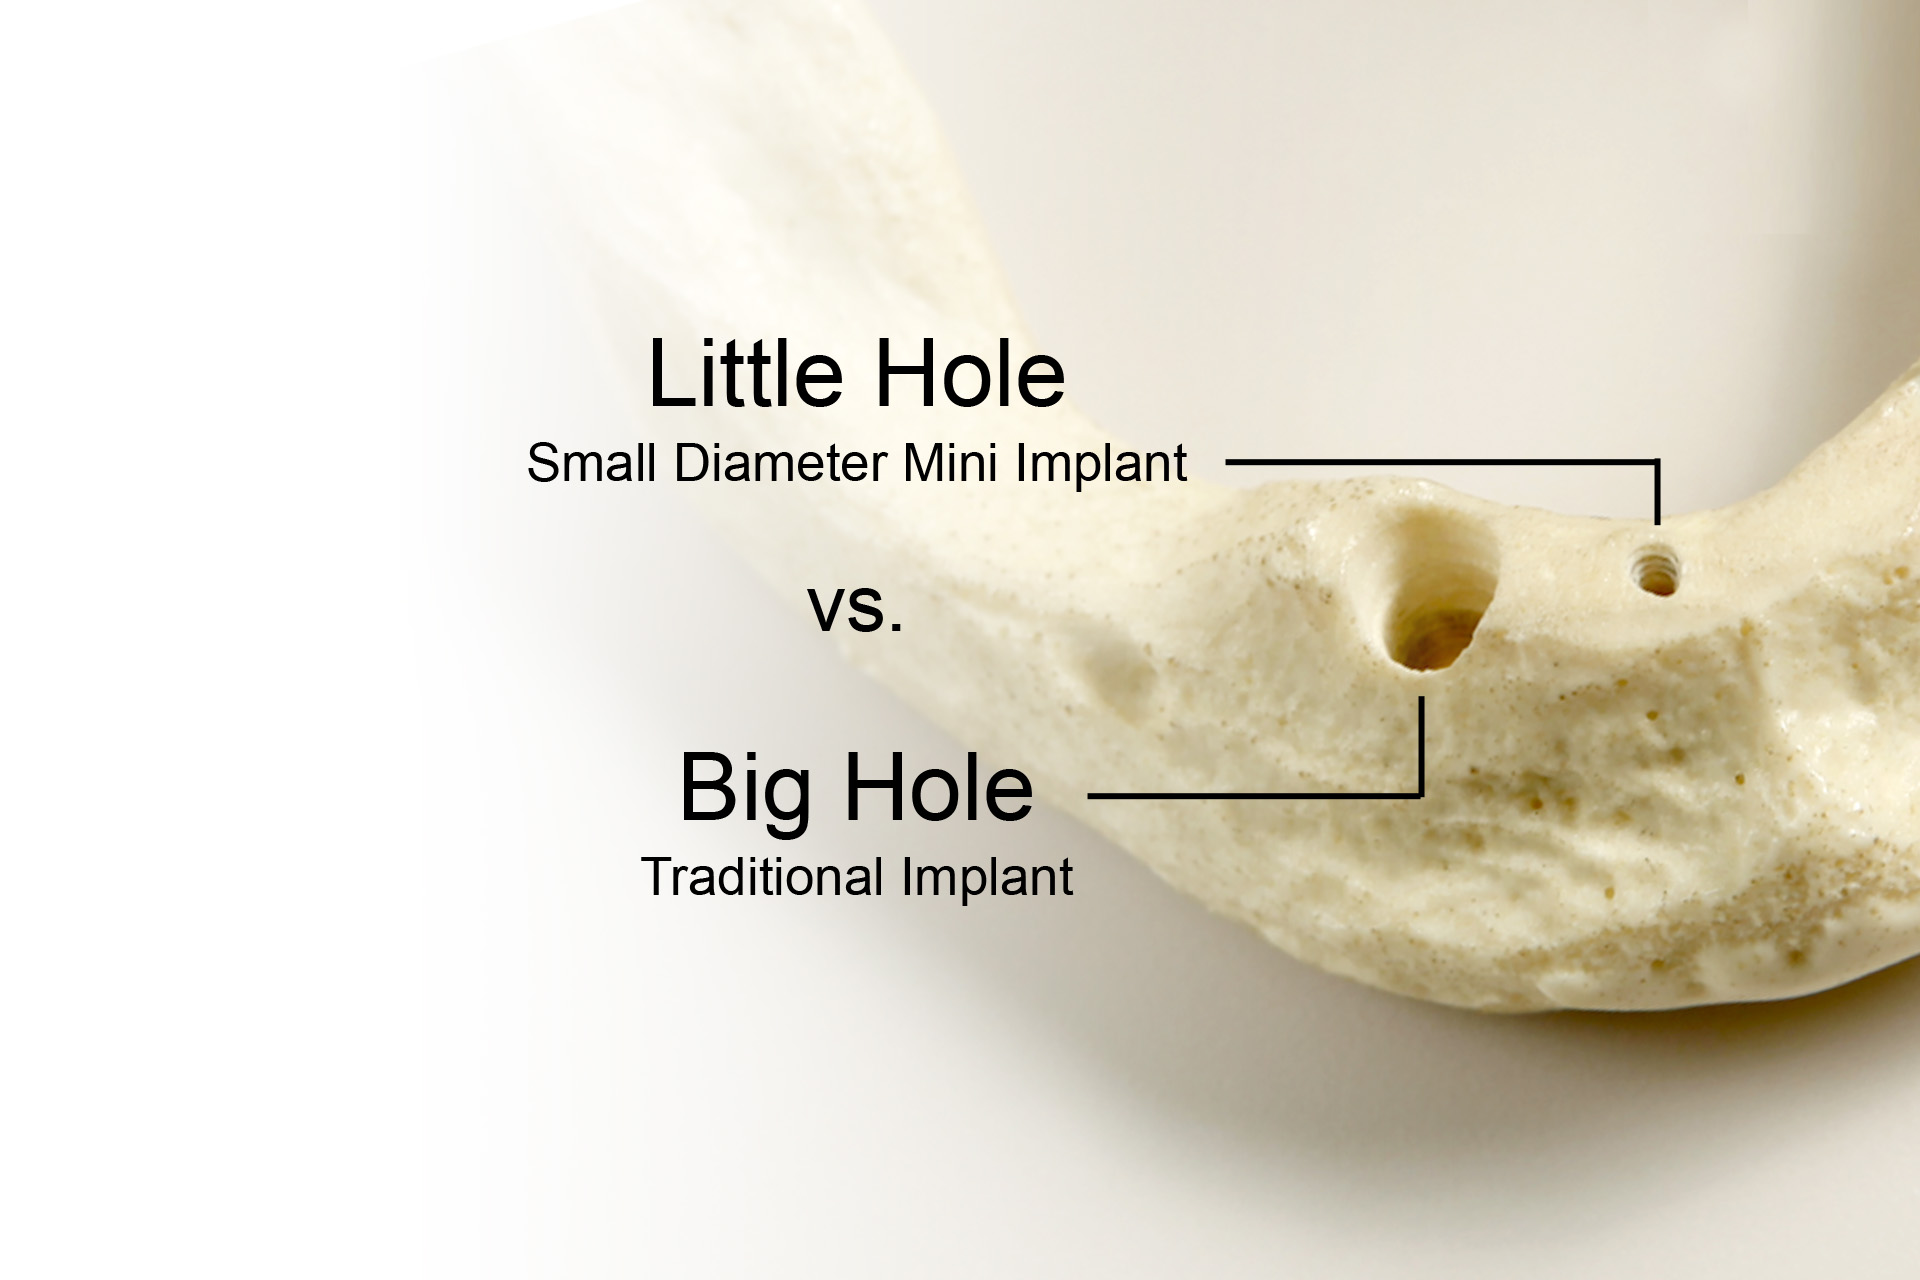

Why Mini Implants?

The mini dental implant procedure is a much less involved process than the conventional dental implants. For this reason, the procedure can usually be completed in one simple dental appointment. In addition to saving time in the dental office, you will have far less discomfort following this procedure due to the minimally involved dental procedure (usually requiring no surgical flaps or sutures). Because the mini dental implants are so time efficient, your dentist is able to perform these procedures at a fraction of the cost associated with the larger conventional dental implants.